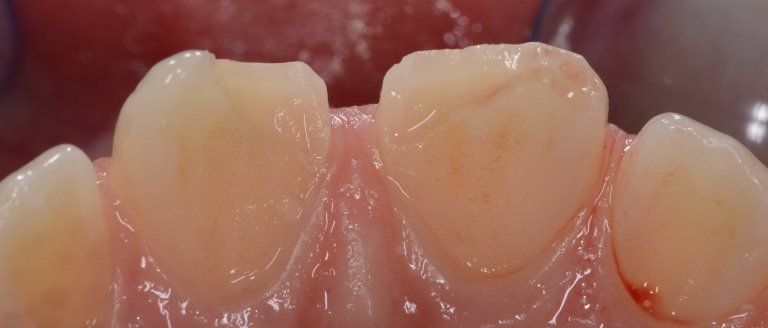

I denti da latte traumatizzati più spesso vanno incontro a necrosi con conseguente cambiamento di colore, divenendo grigiastri, segno della morte delle cellule della polpa dentaria. In altre occasioni, il dente può fratturarsi in maniera più o meno ampia: se il frammento viene ritrovato, potrà essere re-incollato in maniera invisibile, oppure verrà ricostruito con i materiali compositi.